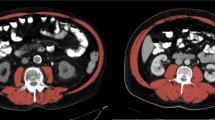

Skeletal muscle loss, referred to as sarcopenia, is a condition characterised by loss of skeletal muscle mass and function. It is a well-established prognostic factor associated with poor outcomes for many cancers7,8,9. Tumour progression is caused by the imbalance between the host and the tumour; it depends on the ability of the host to mount a protective antitumour immune response10. Immune checkpoint inhibitors enhance antitumour immunity by blocking the negative regulator of T cell activation, thus promoting the host immune system’s ability to attack cancer cells. Accordingly, the efficacy of immune checkpoint inhibitors is thought to be heavily dependent on the host’s immune system; body composition is strongly associated with the host’s immune system. However, little is known about the clinical impact of skeletal muscle loss in patients with lung cancer treated with PD-1 inhibitors. Computed tomography (CT) is the gold standard method for analysing skeletal muscle mass because it can be performed as part of daily clinical practice. Measurements of the cross-sectional area of skeletal muscles on abdominal CT at the level of the third lumbar vertebra (L3) are widely used to evaluate sarcopenia7,8,11,12,13. The psoas muscle index (PMI) at the L3 level has been used as a surrogate marker of skeletal muscle mass14,15,16.

Skeletal muscle assessment

The cross-sectional area of the psoas muscle at the caudal end of the L3 level was measured using SYNAPSE VINCENT software (Fujifilm Medical, Tokyo, Japan) before initiating treatment. L3 psoas muscle cross-sectional area was identified and quantified using Hounsfield unit thresholds (−29 to +150)39. The total bilateral psoas area at the L3 level was normalised for height using the following equation:

The PMI cut-off values for sarcopenia in our study were 6.36 (cm2/m2) for males and 3.92 (cm2/m2) for females based on a previous report defining sarcopenia in Asian adults14. The definition of sarcopenia was based only on skeletal muscle mass in the present study.